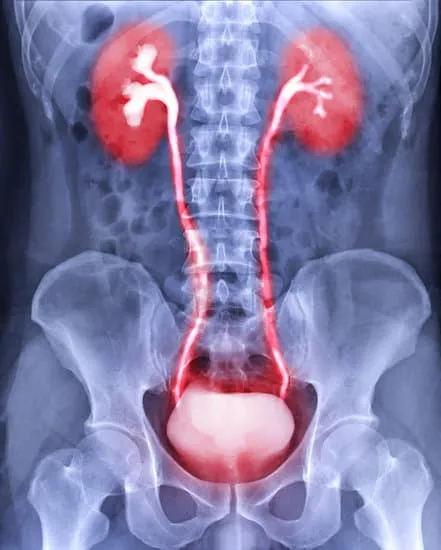

Dr. K. Seethalakṣhmi

Dr.K.Seethalakshmi is the senior Urogynaecologist in addition to Obstetrician & Gynaecologist with 27 years of experience in OBG & 20 years of experience in Urogynaecology. She is an expert in Advanced Urogynaecology and Female Pelvic floor Reconstructive surgeries

Urogynaecology focusses on the management of Female Pelvic Floor disorders, which include Pelvic organ prolapse, Urinary incontinence, pelvic pain and recurrent urinary tract infections, Faecal incontinence& female sexual dysfunction.